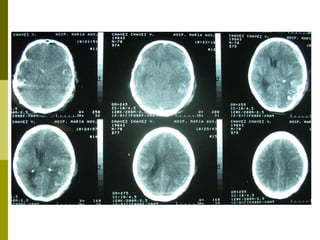

Clasificación Tomográfica del TEC según el National Traumatic Coma Data Bank (TCDB)  Grado, Tipo de lesión, TAC craneal I  Lesión difusa I  Sin patología visible en la TAC II  Lesión difusa II  Cisternas presentes con desplazamientos de la línea media de 0-5 mm y/o lesiones densas presentes. Sin lesiones de densidad alta o mixta > 25 cm3. Puede incluir fragmentos óseos y cuerpos extraños. III  Lesión difusa III (Swelling)  Cisternas comprimidas o ausentes con desplazamiento de la línea media de 0-5 mm. Sin lesiones de densidad alta o mixta > 25 cm3. IV  Lesión difusa IV (Shift)  Desplazamiento de la línea media > 5 mm. Sin lesiones de densidad alta o mixta > 25 cm3. V  Lesión focal evacuada  Cualquier lesión evacuada quirúrgicamente. VI  Lesión focal no evacuada  Lesión de densidad alta o mixta >25 cm3 no evacuada quirúrgicamente. Marshall L., Gautille R, Klauber M et al. The outcome of severe closed head injury. J. Neurosurg. 75 (S):528.1991.

Resultados Según la clasificación tomográfica del TEC, las lesiones  más frecuentes fueron:  Categoría VI TCDB: 10 - 28%.  Categoría V TCDB:  7 – 19% Categoría IV TCDB: 1 –3% Hematoma Extraaxial: 12 – 33%  Lesiones mixtas:  14 – 39%

Clasificación Tomográfica delTEC según el National Traumatic Coma Data Bank (TCDB) Grado, Tipo de lesión, TAC craneal I Lesión difusa I Sin patología visible en la TAC II Lesión difusa II Cisternas presentes con desplazamientos de la línea media de 0-5 mm y/o lesiones densas presentes. Sin lesiones de densidad alta o mixta > 25 cm3. Puede incluir fragmentos óseos y cuerpos extraños. III Lesión difusa III (Swelling) Cisternas comprimidas o ausentes con desplazamiento de la línea media de 0-5 mm. Sin lesiones de densidad alta o mixta > 25 cm3. IV Lesión difusa IV (Shift) Desplazamiento de la línea media > 5 mm. Sin lesiones de densidad alta o mixta > 25 cm3. V Lesión focal evacuada Cualquier lesión evacuada quirúrgicamente. VI Lesión focal no evacuada Lesión de densidad alta o mixta >25 cm3 no evacuada quirúrgicamente. Marshall L., Gautille R, Klauber M et al. The outcome of severe closed head injury. J. Neurosurg. 75 (S):528.1991.

Resultados Según laclasificación tomográfica del TEC, las lesiones más frecuentes fueron: Categoría VI TCDB: 10 - 28%. Categoría V TCDB: 7 – 19% Categoría IV TCDB: 1 –3% Hematoma Extraaxial: 12 – 33% Lesiones mixtas: 14 – 39%